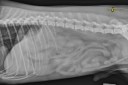

Il nous fait un cinéma ou doit-on l’envoyer en chirurgie ?!?